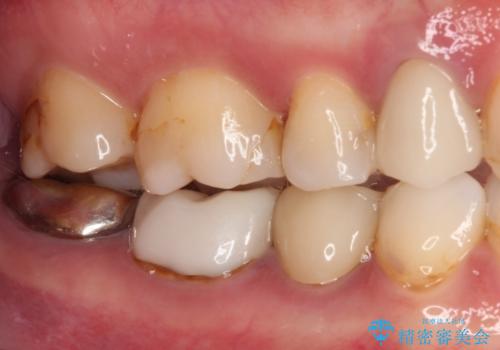

- 奥歯の詰め物や周辺の歯が欠けてしまったとのことで来院された患者様です。

上顎は、元々の詰め物が小さく、欠けた範囲も大きくなかったため、セラミックインレーにて修復治療を行うこととしました。

一方下顎は、元々のむし歯の範囲が広かったため、長期的な予後を踏まえ、セラミッククラウンにて補綴治療を行うこととしました。